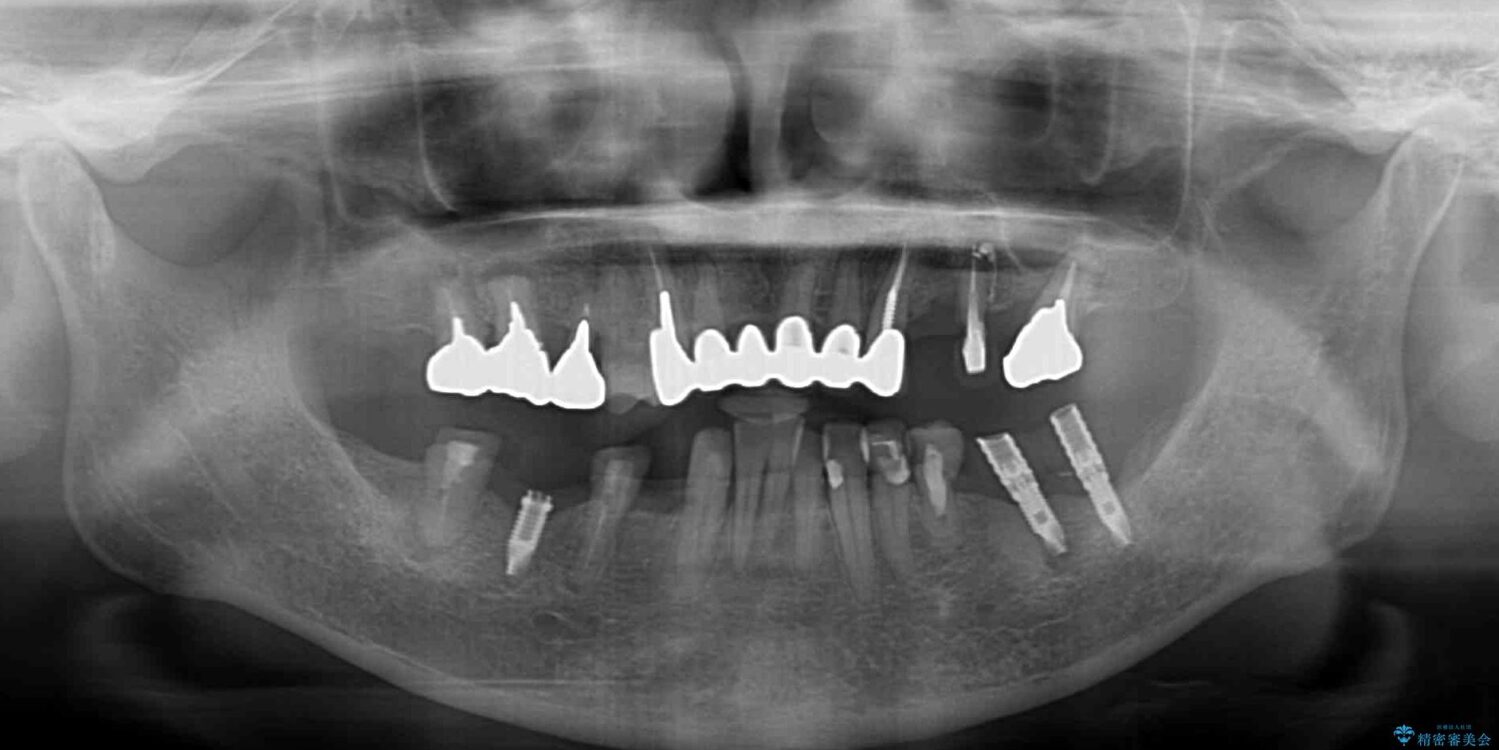

ご主人が当院に通院されていたことで、ご紹介により来院されました。 以前通院していた医院で、奥歯のインプラント埋入、前歯部のインビザライン矯正を行ったものの、そのまま放置してしまったとのことで来院された患者様です。

下顎前歯や上顎奥歯などをワイヤー装置により部分矯正を行い、歯列を整えた上でインプラント部分を含めてオールセラミッククラウンにて補綴治療を行うこととしました。

インプラント上の仮歯がボロボロになり、前歯に非常に負担のかかる状態であったため、早急に奥歯の仮歯を修復し、矯正治療、奥歯の補綴治療、前歯の補綴治療と順々に進めて行きました。

治療前

• 放置したインプラントとインビザライン 全顎リカバリー治療 治療前画像